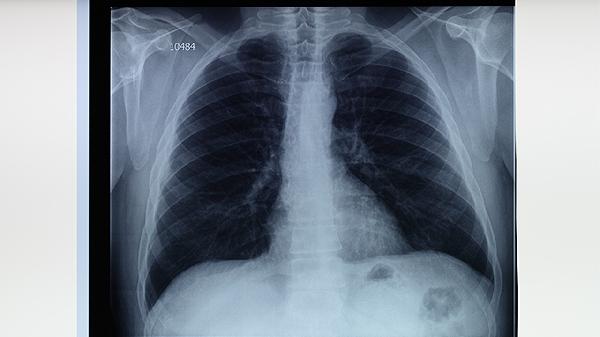

肺結(jié)核患者可選用百部、白及、黃芩三味中藥輔助治療,具有抑菌殺蟲、收斂止血、清熱燥濕的功效。